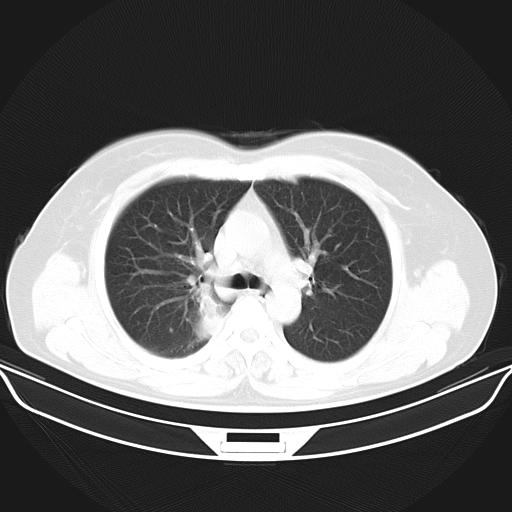

标题: CT22224:肺部肿块

f,48,主因咳嗽咳血来我院检查,无发热。

1)右肺下叶背段团块状软组织密度影;建议抗炎治疗后复查排除肿瘤性病变。2)右侧少量胸腔积液。

谈一谈个人的看法:机器性能应该不错,可惜扫描方法不太正确,即没有及时薄层扫描图像,也没有增强检查,这样的检查方法不正确的图片拿来研究只能是猜一猜:右肺下叶阻塞性改变,建议进一步检查删除肺癌。

支气管镜检查未见异性细胞,抗炎治疗20天,肿块明显缩小。